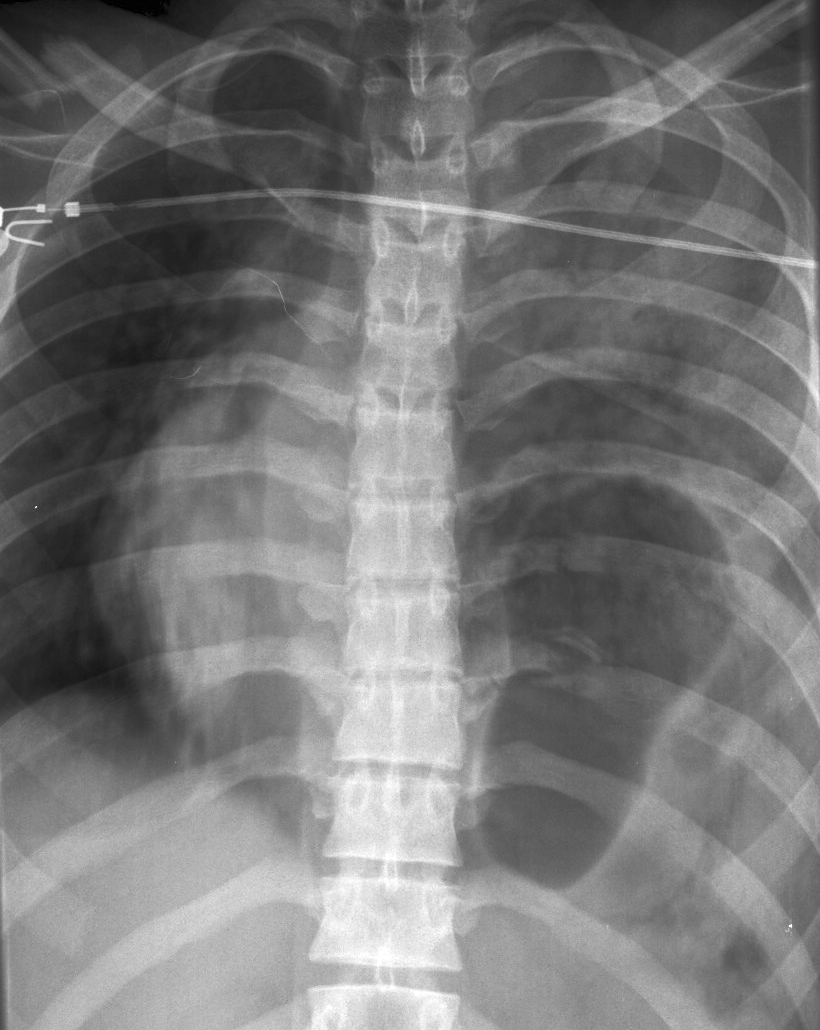

Gallery Blunt Chest Trauma Rupt HD Case 9b

Case 9b

Date: 11/19/2005